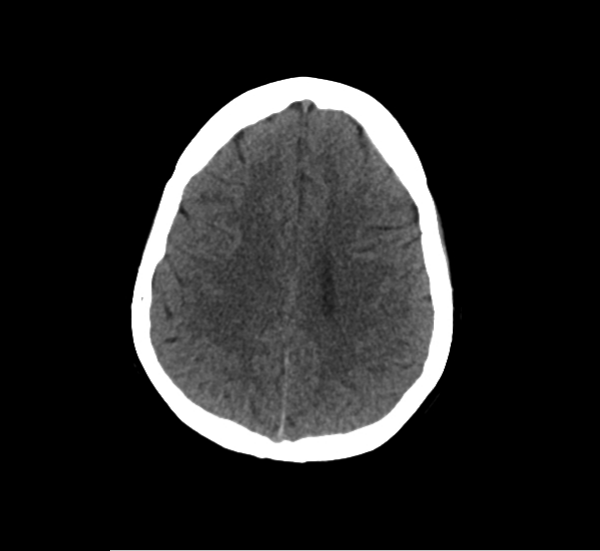

CT Brain Anatomy